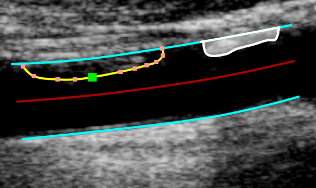

images/download/thumbnails/388694064/CVS_CAR_PlaquesBorders-version-1-modificationdate-1761817174877-api-v2.png

Modification des bordures

• Survolez la bordure à modifier.

• Cliquez et faites glisser un des points de la bordure.